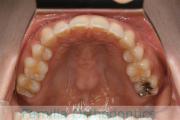

No.22V-299

- 上顎前突

- 叢生

- 30歳

- 女性

- 上:

- 44

- 下:

- 主な使用装置:

- FEA 022

- 治療にかかった費用:

- 90万円

上の出っ歯、口が閉じにくい、下の前歯のガタガタを治したいということで来院されました。上顎から左右小臼歯を、下の前歯は凹凸が非常に強いので、こちらから一本抜歯を行いました。2年強、30回程度の通院が必要でした。

成人になってからの叢生(でこぼこ、凹凸、ガタガタ)は、保定をしっかりしないと後戻りをしてしまうリスクが高いです。